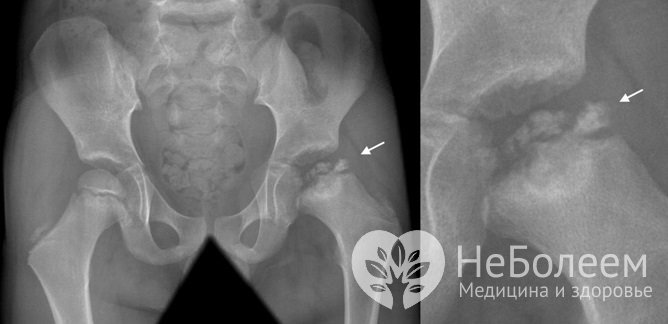

Основной метод исследования – рентгенография тазобедренных суставов. Снимки выполняются в стандартных проекциях и проекции Лауэнштейна («позе лягушки»). Рентгенологическая картина при данном заболевании зависит от выраженности патологического процесса и его стадии.

Болезнь Пертеса на рентгеновском снимкеБолее информативным диагностическим методом на ранней стадии болезни Пертеса является магнитно-резонансная томография тазобедренного сустава, позволяющая с большой точностью оценить состояние костных и мягких тканей.